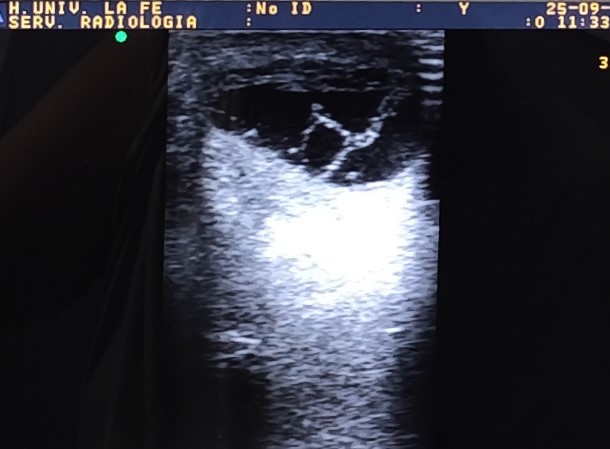

Hombre de 68 años que consulta por lesión quística/nodular en codo izquierdo de varios años de evolución con incremento de molestias al roce y apoyo en las últimas semanas. Sin otra sintomatología por aparatos ni otras articulaciones afectas.

Descripción de los hallazgos ecográficos y las imágenes más relevantes para la resolución del caso

Diagnóstico diferencial: quistes sinoviales, bursitis u otras masas de tejidos blandos.

La gota es una enfermedad metabólica crónica que causa depósitos de cristales de urato en tejidos blandos y articulaciones; este caso clínico ilustra un ejemplo, donde un tofo nodular en el codo se convierte en el motivo principal de consulta. La ecografía clínica permitió detectar las características típicas de dicha enfermedad, facilitando un diagnóstico presuntivo sólido y guiando de forma adecuada las decisiones terapéuticas.